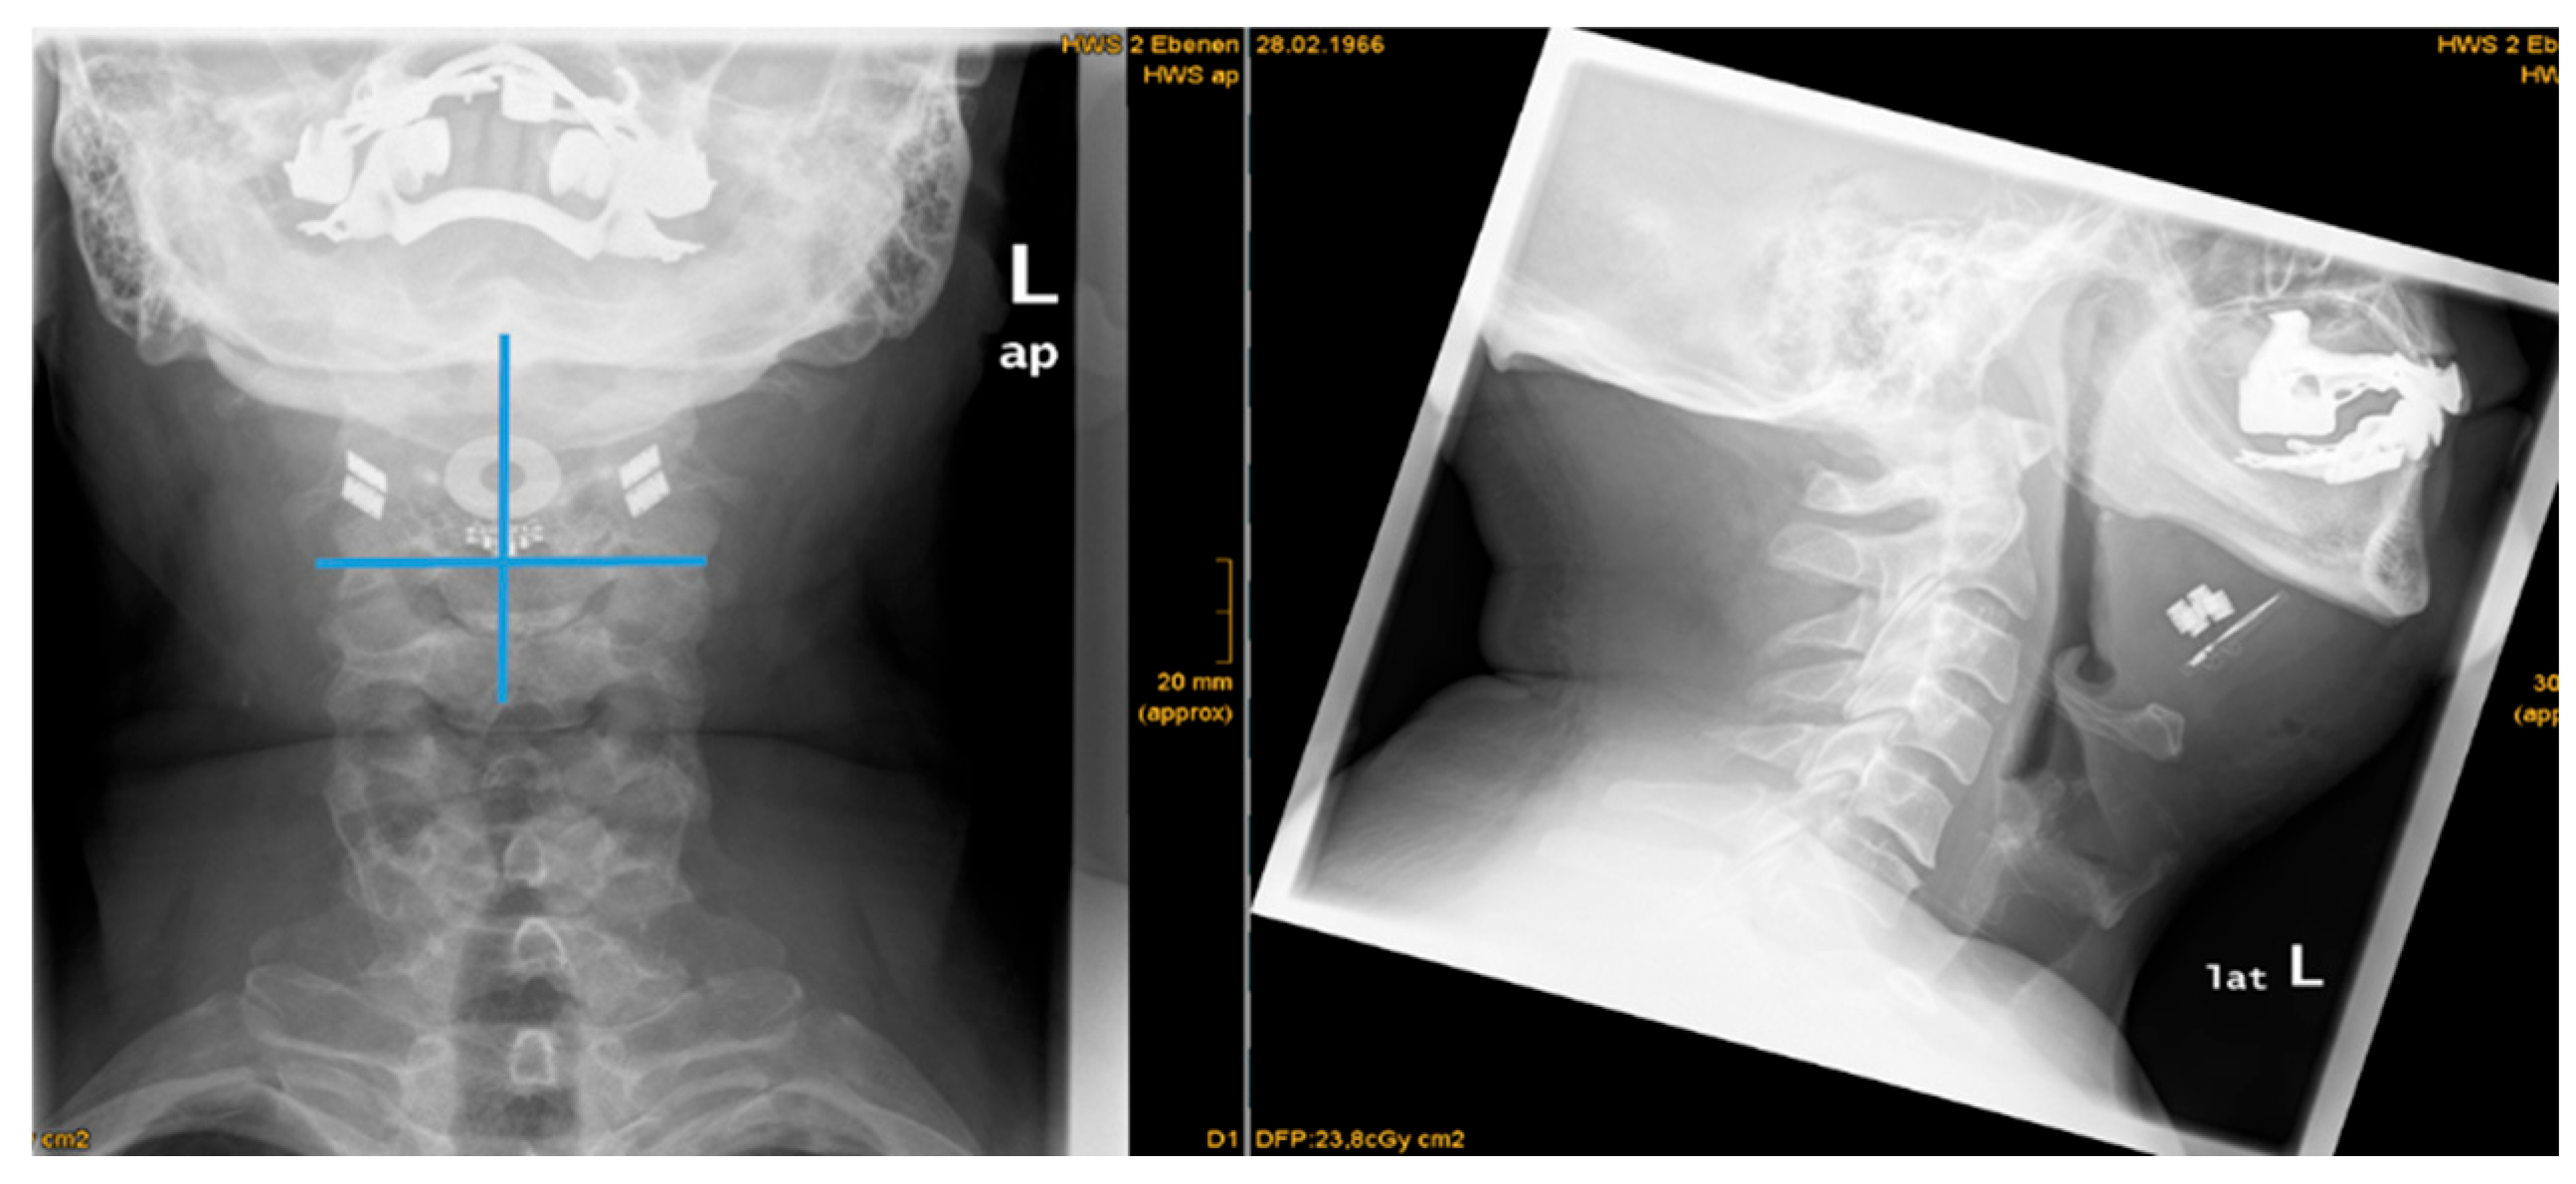

| 1 | 33 | 26 | yes | yes | yes | moderate | no | yes | 87,3 | 28,7 | 56,4 | 15,2 | 7,9 | 22,6 | -14,7 | asymmetry | 64,9 | proximal | proximal |

| 2 | 47 | 30 | yes | yes | yes | strong | no | yes | 94,1 | 45,7 | 57,0 | 19,0 | 18,7 | 19,3 | -0,6 | symmetry | 70,4 | proximal | proximal |